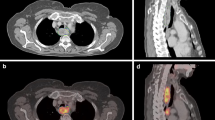

Contouring was performed using specialized software (RTx, Mirada Medical, Oxford UK). PET and CT images were displayed using preset window levels and/or colour scale per a standardized institutional protocol (Fig. 1). Patients were contoured per the National Cancer Research Institute (NCRI) UK NeoSCOPE trial protocol [18]. The tumour length and outlines were derived from the diagnostic imaging which included an Endoscopic Ultrasound, contrast-enhanced CT and 3D PET-CT. The longest tumour dimension was used for outlining. The maximal length of the tumour with specific reference to an anatomical structure e.g. carina or superior aortic arch was defined on all imaging techniques. This enabled the oncologist and radiologist to identify the superior and inferior extent of the diseased oesophagus in relation to these structures; thereby allowing them to outline this segment of the entire circumference of oesophagus to be outlined. All the 4D CT and PET scans included at least one of the reference structures (e.g. superior aortic arch or carina) and therefore the target volumes were produced consistently on each of these datasets with reference to these structures [2]. Local nodal involvement was included in the target volume but more distant nodes were not. An experienced radiation oncologist contoured all target volumes with access to clinical details and standard-of-care imaging; PET-derived contours were generated by the same radiation oncologist contouring with an experienced dual-certified Nuclear Medicine Physician/Radiologist. GTVs were delineated on i) 10-phase planning 4D CT, ii) 10-phase 4D CT inherently co-registered to 3D PET-CT acquired at the same scan session and iii) 4D PET-CT. CTV was delineated and trimmed to anatomical boundaries (vertebrae, pericardium, pleura). 4D datasets from each series were used to generate an internal target volume (ITV) encompassing effects of physiological motion on the CTV. Expansion to PTV was the ITV of each series with a 5-mm margin in all directions. (Fig. 2). A minimum interval of 2 weeks was specified between delineation using each different methodology for each patient, to minimize any potential for intra-observer recall.